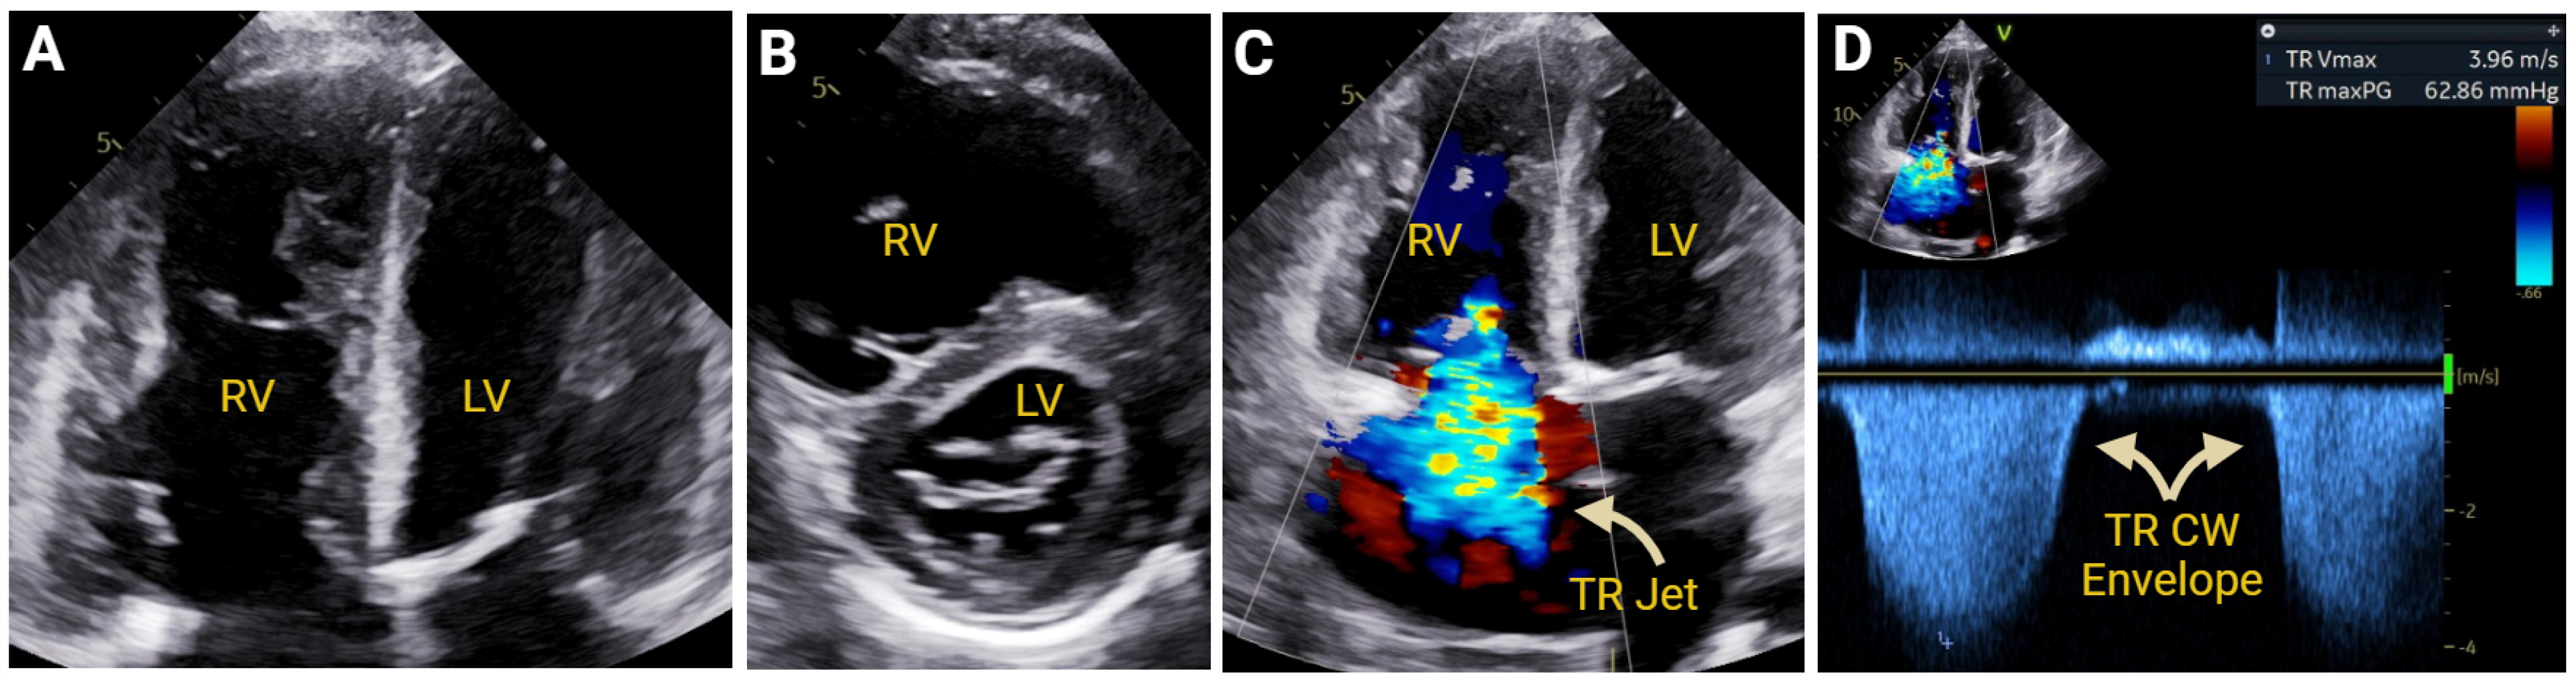

7.2.1. Pulmonary Hypertension

7.2.4. Pulmonic and Tricuspid Valvular Disease

- Clement, A.; Tomaselli, M.; Badano, L.P.; Hadareanu, D.R.; Radu, N.; Penso, M.; Caravita, S.; Baratto, C.; Fisicaro, S.; Delcea, C.; et al. Association With Outcome of the Regurgitant-Volume Adjusted Right Ventricular Ejection Fraction in Secondary Tricuspid Regurgitation. J. Am. Soc. Echocardiogr. 2025, 38, 451–464. [Google Scholar] [CrossRef] [PubMed]

- Hahn, R.T.; Brener, M.I.; Cox, Z.L.; Pinney, S.; Lindenfeld, J. Tricuspid Regurgitation Management for Heart Failure. JACC Heart Fail. 2023, 11, 1084–1102. [Google Scholar] [CrossRef] [PubMed]